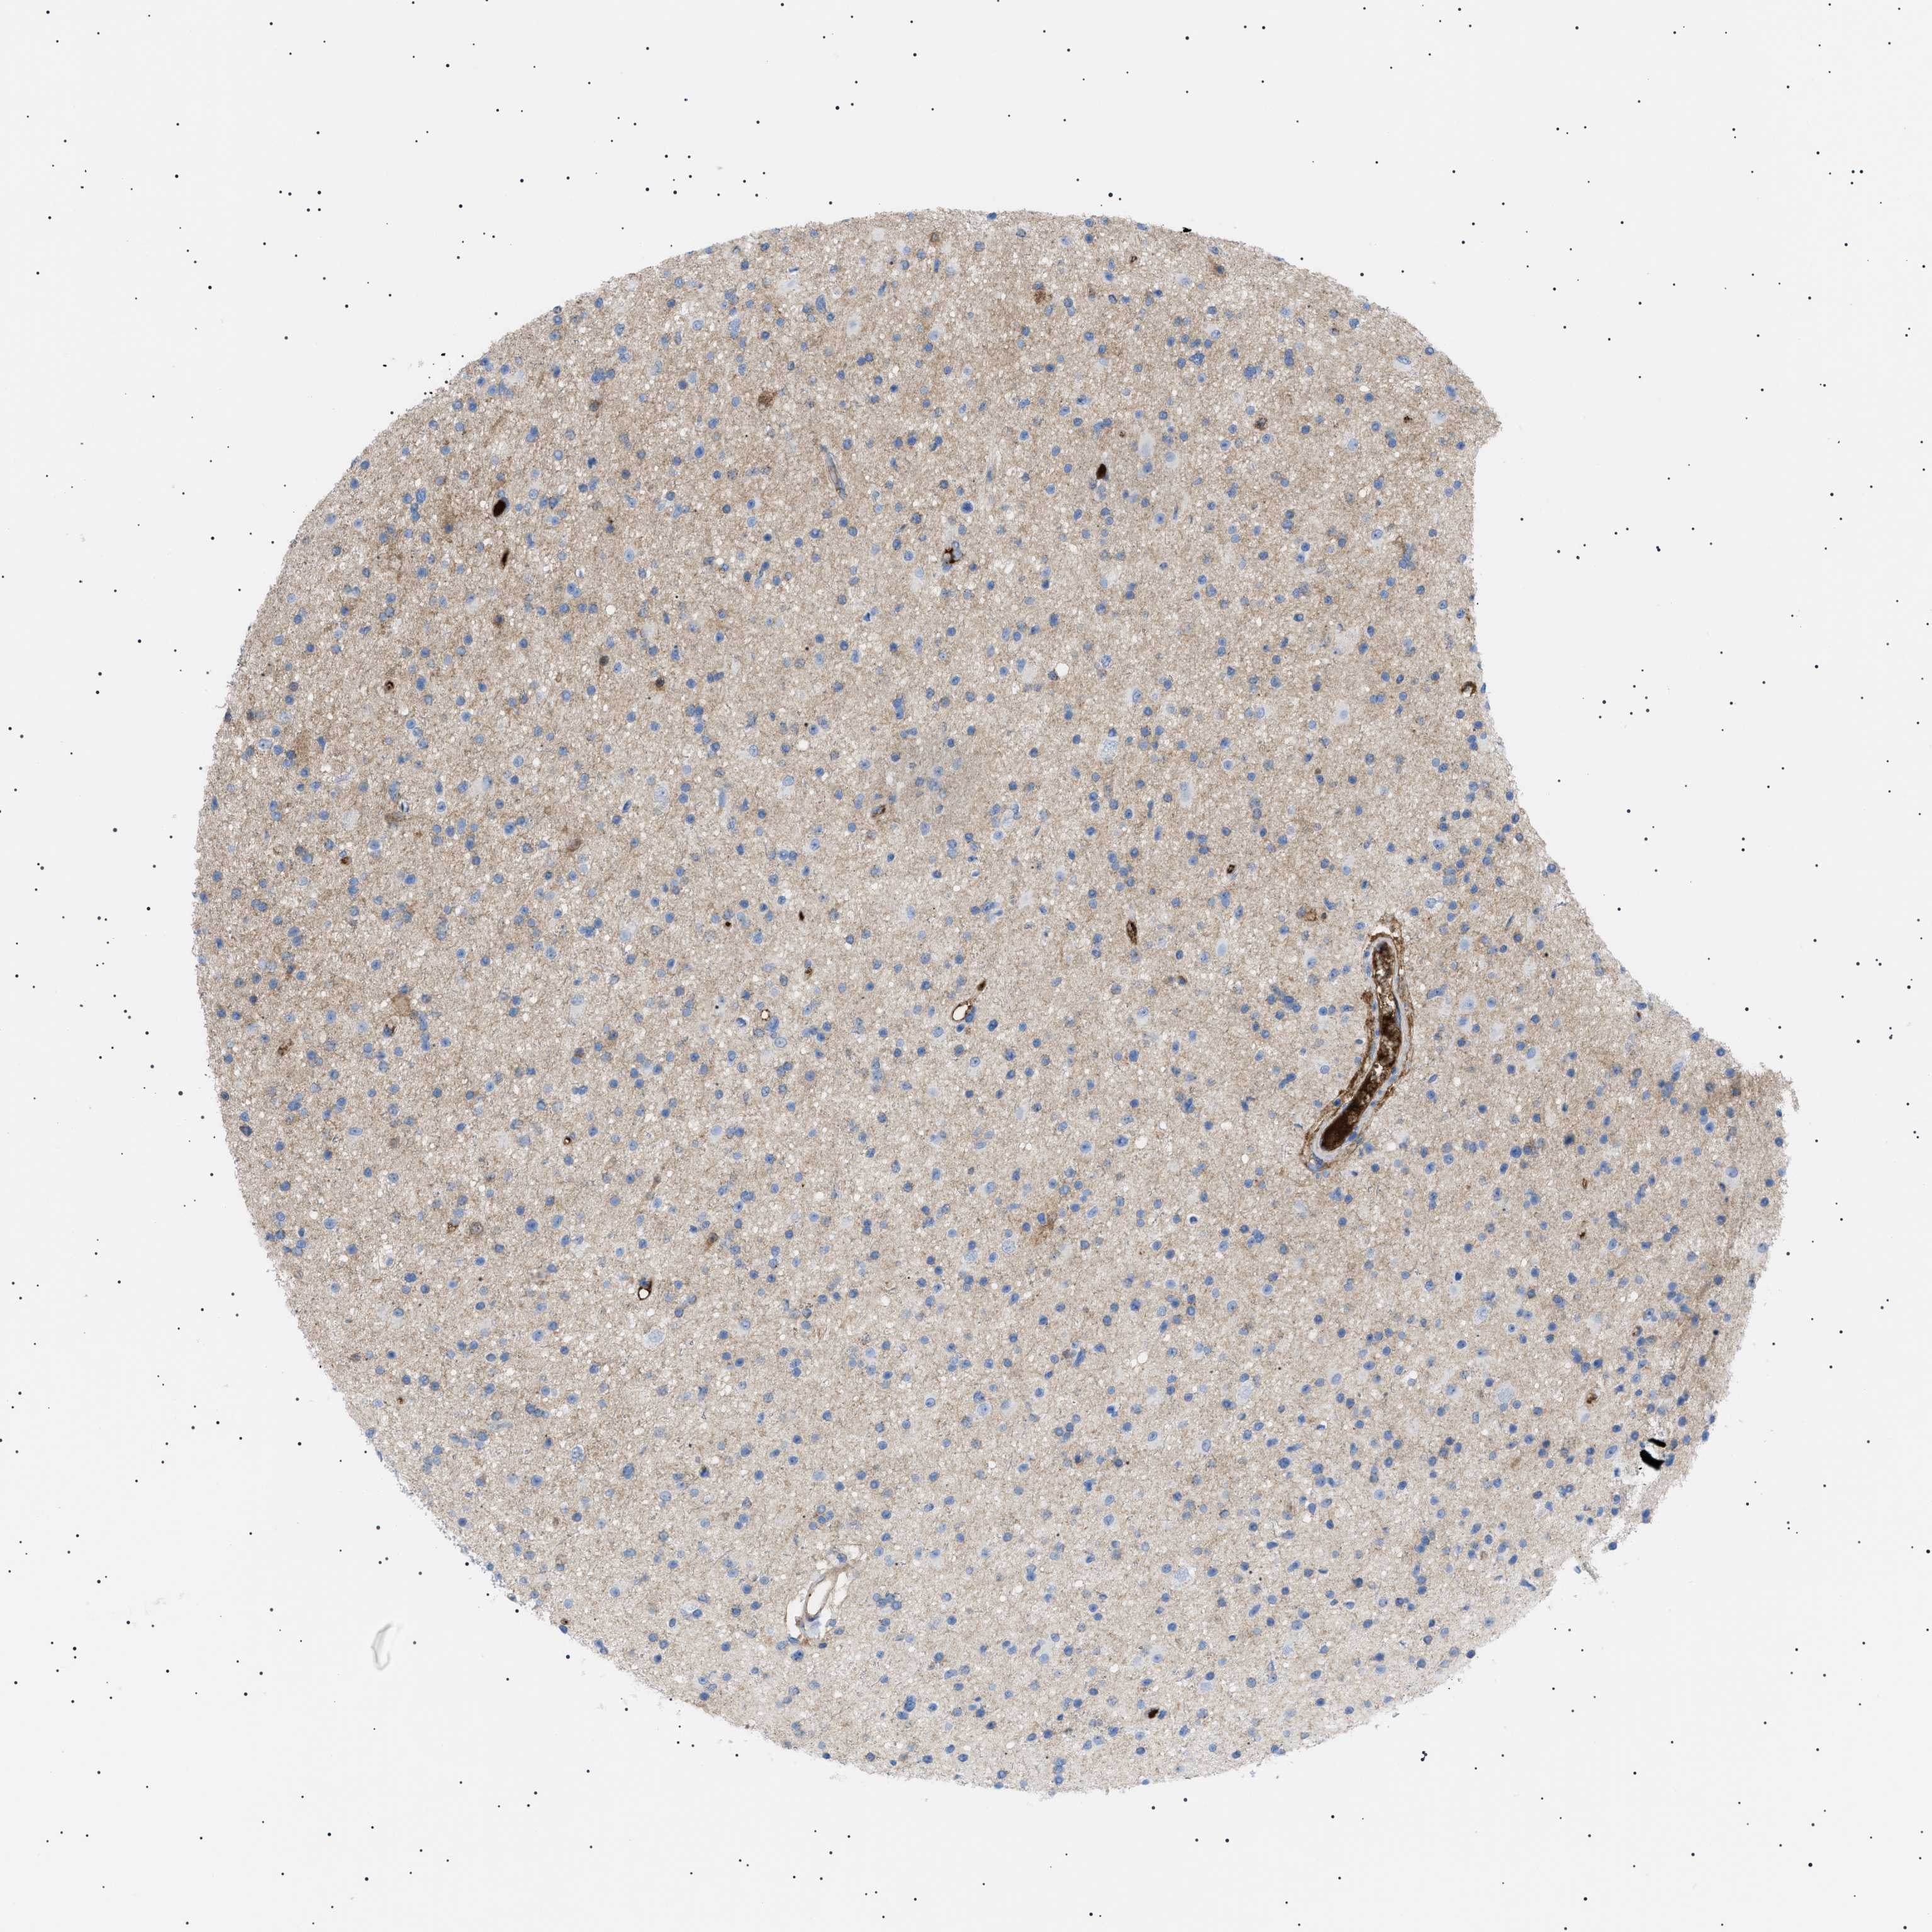

GLIOMA - Protein expressioni

A mouse-over function shows sample information and annotation data. Click on an image to view it in a full screen mode. Samples can be filtered based on level of antibody staining by selecting one or several of the following categories: high, medium, low and not detected. The assay and annotation is described here.

Note that samples used for immunohistochemistry by the Human Protein Atlas do not correspond to samples in the TCGA dataset.

Antibody stainingi

Antibody staining in the annotated cell types in the current human tissue is reported as not detected, low, medium, or high, based on conventional immunohistochemistry profiling in selected tissues. This score is based on the combination of the staining intensity and fraction of stained cells.

Each image is clickable and will lead to virtual microscopy that enables deeper exploration of all samples and also displays staining intensity scores, fraction scores and subcellular localization as well as patient and tissue information for each sample.

Antibody HPA060604

Antibody CAB016072

Glioma, malignant, High grade